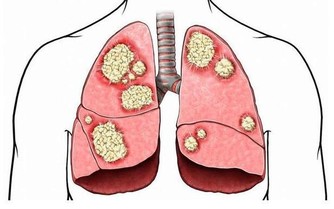

女性每年有20萬人口死於婦科疾病,其實她們不是死於婦科疾病,是死於對自己的無知! 據世界衛生組織對中國婦女的調查:41%的育齡女性患有不同程度的婦科炎症,而已婚女性發病率更高達70%。下面是一位婦產科主任醫師的筆記,讓我們一起看下。 1.女性生殖系統分兩大部分,一部分是外生殖器,另一部分是內生殖器=。 2.子宮是孕育生命的一個重要場所,未孕時子宮有雞蛋那麼大,一旦受孕,子宮像氣球一樣膨脹,等到了分娩,子宮就要收縮回來,也就像拳頭這麼大了,這個時候的子宮就布滿了皺褶和隱窩,也已經不再光滑了,這些皺褶隱窩裡就要殘留垃圾。 ★子宮到底殘留多少垃圾? ①生兒育女的垃圾--羊水垃圾、惡露垃圾 ②夫妻生活垃圾 ③每個月內膜沒脫落干淨的垃圾 ④再加上內源體外源體新陳代謝的垃圾 這些垃圾日積月累,堆積成山,久而久之它就產生了毒素,萬病起源於毒素,也就是現在為什麼有那麼肌瘤啊,囊腫啊,內膜炎啊等等婦科疾病的原因。 以前的人為什麼沒有這麼多毛病呢?那是因為生育多,後一次把前一次的垃圾衝出來,沒有陳年垃圾,加上不斷地母乳喂養,乳腺不斷地疏通,固難以造成阻塞,加上環境因素,婦科疾病沒有現在這麼多。 3.避孕環有沒有傷害? 說沒有,是不可能的。男人如果可以體貼女人一點,不上環當然是最好的。 有的人認為國內的技術不好,要去美國上環,那是很可悲的誤區。西方人的體格大於中國人,因此環的規格比國內大,完全不適合黃種人的子宮。結果引發更多後遺症,一般還很難找出這個原因。 另外女性要注意,避免避孕環超期服役,正常戴20年,很多人過了20年、30年甚至終身不摘。臨床上有很多糖尿病其實是避孕環超期服役造成的假像。摘環後便沒事。但如果超期服役時間太長,金屬避孕環已經鈣化進入盆腔,就摘不了了,假性糖尿病也就難以解決。 4.知道為什麼女人比男人壽命長嗎? 就因為女人比男人多一個排毒器官叫子宮,所以別輕易說給我把子宮拿掉,有子宮和沒子宮生命相差十到十五年。 5.不建議女性用天天護墊。 其實衛生巾如果不能抑菌,就是最滋生細菌的。你以為這個上面吸收了你排出來的異物,但其實你是讓細菌留在巾體上,讓細菌在體溫和潮濕的環境中,有機會滋生並且感染你。特別在經期,如果有經血的情況下,這種有害菌滋生得更快。 你怎麼知道細菌滋生得快?有異味,變質的血腥味就是細菌腐蝕血液的結果。這就是為什麼經期其實是婦女炎症的高發期。 6.為什麼有的順產的人傷口不容易好? 其實就是細菌滋生影響傷口癒合。現在的衛生巾很多因為棉材都不太好,所以多用熒光劑漂白,熒光劑本身就是致癌的,且可以通過毛孔進入毛細血管參與血液循環。這種化學的東西很難通過代謝排出,殘留在身體裡,紊亂免疫系統。 7.不要人為的選擇剖腹產,女人的腹腔只要打開,一定是大傷元氣。 因為女人的腹腔部位有一個非常重要的部位叫「胞中穴」,還要在子宮上劃一刀!剖腹產的女性她的子宮收縮一定沒有順產的好,她的皺褶隱窩一定比平常女性多。醫生若是有輕易建議你破腹產的,那一定是因為效益的關系。誰會中招呢?那些無知的,膽小怕痛的。 8.月經提前得越多,說明氣虛現像越嚴重。 月經提前嚴重的都會造成貧血,血小板減少,千萬不要忽視月經;如果推後,說明宮寒血冷越嚴重,而且也最容易造成關節不好。 9.急性宮頸炎一般是月經期過度性生活而造成的。 月經來之前宮頸要微張,這個時候我們的毛細血管全部處於擴張狀態,如果有夫妻生活馬上會讓它充血,充血就會產生炎症,也就是急性宮頸炎。因宮頸沒有疼覺神經,我們女性沒有感覺,時間一長就變成慢性宮頸炎。 10.子宮頸癌用眼睛分辨不出來。 醫生用眼睛是分辨不出來的,只有去做一個檢查--就是切片,或者是活檢,看看裡面有沒有癌細胞,如果有,早期把宮頸拿掉,中期把子宮拿掉,晚期對不起,到西天去報到,沒有任何辦法的。 11.女性只有一種癌症沒有最佳治療期就是--子盆腔癌。 子盆腔癌雖然發病率低,但是死亡率高,也是很可怕的。所以建議大家不要坐太多,現在的亞健康缺就缺兩條腿走路太少了,屁股坐得太多了,盆腔炎會引起盆腔積液,慢慢發展成盆腔癌。 12.宮頸癌和乳腺癌現在號稱兩大天敵。 也就是說35歲到50歲之間是婦科病高發年齡段,30歲--40歲是高危年齡段,所以婦檢太重要了!建議大家30歲以下,每年婦檢一次,如果說是35歲上的,特別是35--50之間的女性,建議婦檢每年兩次。 宮頸癌、子宮癌,子宮內膜癌包括乳房癌都有最佳治療期。所以女性炎症只要早期發現,早期治療,早期根除,女性的癌症一定是離我們遠遠的。 13.宮頸肥大居然還說沒問題? 醫生說沒問題是說沒有像梅艷芳那樣的大問題,不是真的沒問題,宮頸肥大就已經說明宮頸炎出現了,只是沒有那麼嚴重而已,但對於你來講,這個時候是最好治癒的。 14. 我們很多女性都知道便後要洗手,其實便前洗手比便後洗手更重要。 隨著年齡的增長,我們有兩道天然的防線都沒有了,第一道防線就是處女膜,第二道防線就是PH值,酸堿度開始減弱,最容易感染。 15.為什麼洗液是不能一直用? 因為裡面的抗生素破壞PH值。也就是自身的免疫平衡會被破壞。 很多人都跟著廣告走,以為可以洗一洗就能夠把有害菌殺死了。其實你真正殺死它了嗎?沒有。相反,婦科炎症會越來越重。起初,許多人只是外皮上感染。不洗還好,一洗炎症往裡頭走。越走越深,就到宮頸了,就變成宮頸炎。 16.無論對女性還是對孩子而言,順產一定是最好的。 子宮劇烈收縮會使免疫蛋白IgG通過主動轉運的方式通過胎盤進入胎兒體內,因此IgG含量比剖宮產顯著增高,從而彌補了新生兒體液免疫的不足,順產的寶寶免疫力就是會好一些。 17.陰 道炎是最好治癒的。 只要早期發現,因為陰 道靠我們的外陰最近,沒有後穹隆沒有旮旮瘩瘩的地方,所以也是最好治療,不要拖延。 趕快把知識分享出去,女性每年有20萬人口死於婦科疾病,其實她們不是死於婦科疾病,是死於對自己的無知!!